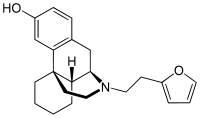

Others

- Butorphanol

Structures

| Other Morphinans | ||||

Butorphanol Butorphanol |